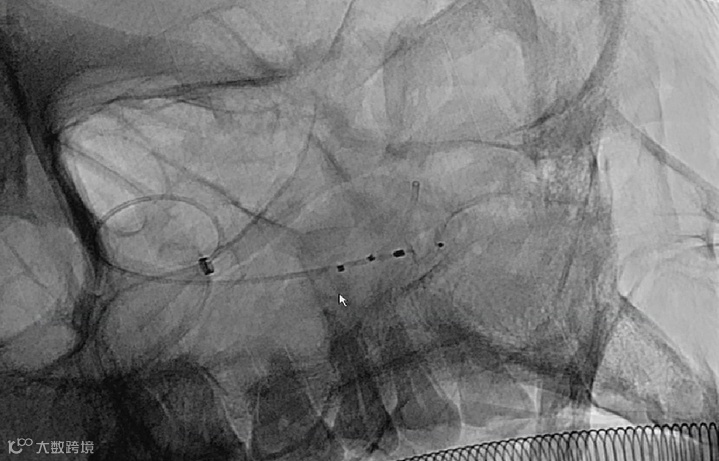

经初次测量评估,选用WEB™ SL7×3mm进行动脉瘤栓塞治疗。

缓慢推送WEB™ SL 7×3mm至微导管顶端后,暂停,WEB™和VIA™微导管的推送力与回弹力达到平衡后,再进行后续WEB™在瘤内的精准释放。

缓慢推送 WEB™至种子-萌芽状态后, WEB™顺着瘤壁慢慢滑向瘤中,缓慢释放 WEB™至开花再到完全释放状态。

WEB™释放完成后,影像显示WEB™ 7×3mm与动脉瘤不匹配,更换WEB™ SL5×3mm与支架配合使用。